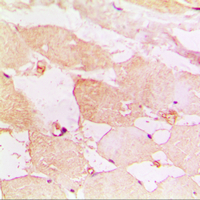

Immunohistochemical analysis of CD183 staining in human muscle formalin fixed paraffin embedded tissue section. The section was pre-treated using heat mediated antigen retrieval with sodium citrate buffer (pH 6.0). The section was then incubated with the antibody at room temperature and detected using an HRP conjugated compact polymer system. DAB was used as the chromogen. The section was then counterstained with haematoxylin and mounted with DPX.